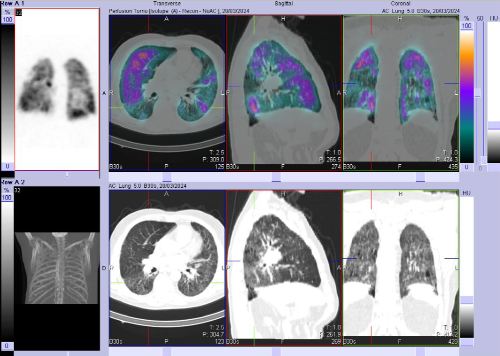

/ Obr. č. 8-10: ldCT plic v rámci vyšetření SPECT/CT. /

SPECT/CT potvrzuje tyto perfuzní defekty. Na ldCT je dále patrná Vámi popisovaná nespecifická intersticiální pneumonie, taktéž emfyzém, to však nevysvětluje diskrepanci mezi perfuzí a ventilací. Jde tedy o tzv. V/P mismatch.